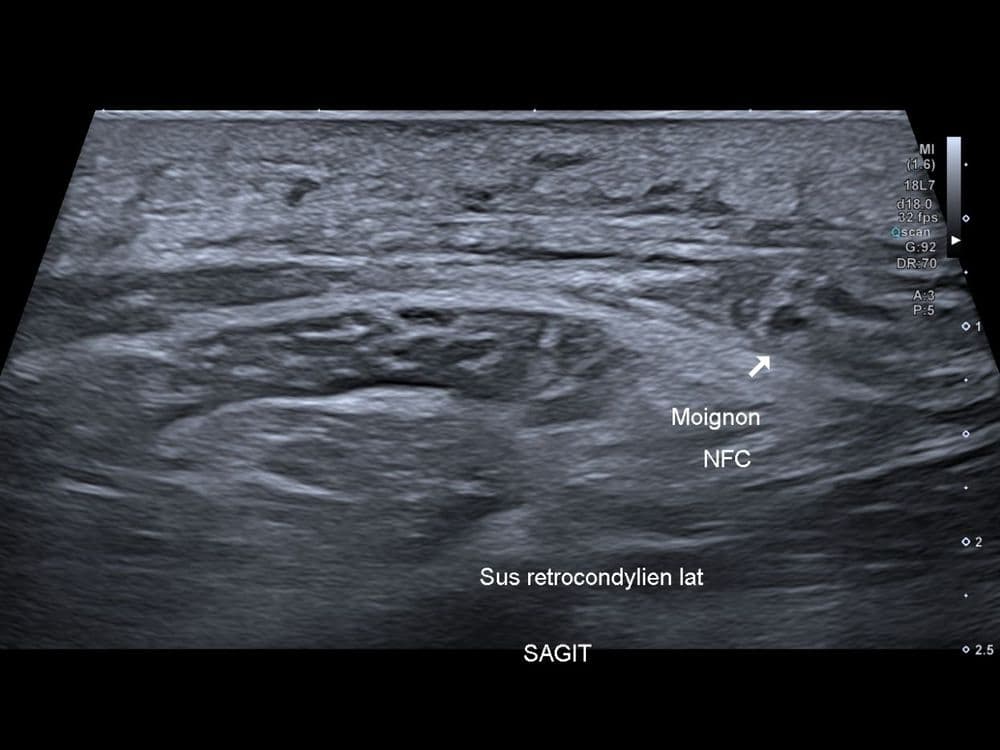

Jeune rugbyman présentant un traumatisme complexe du genou droit suite à un violent placage durant un match.

USMRI